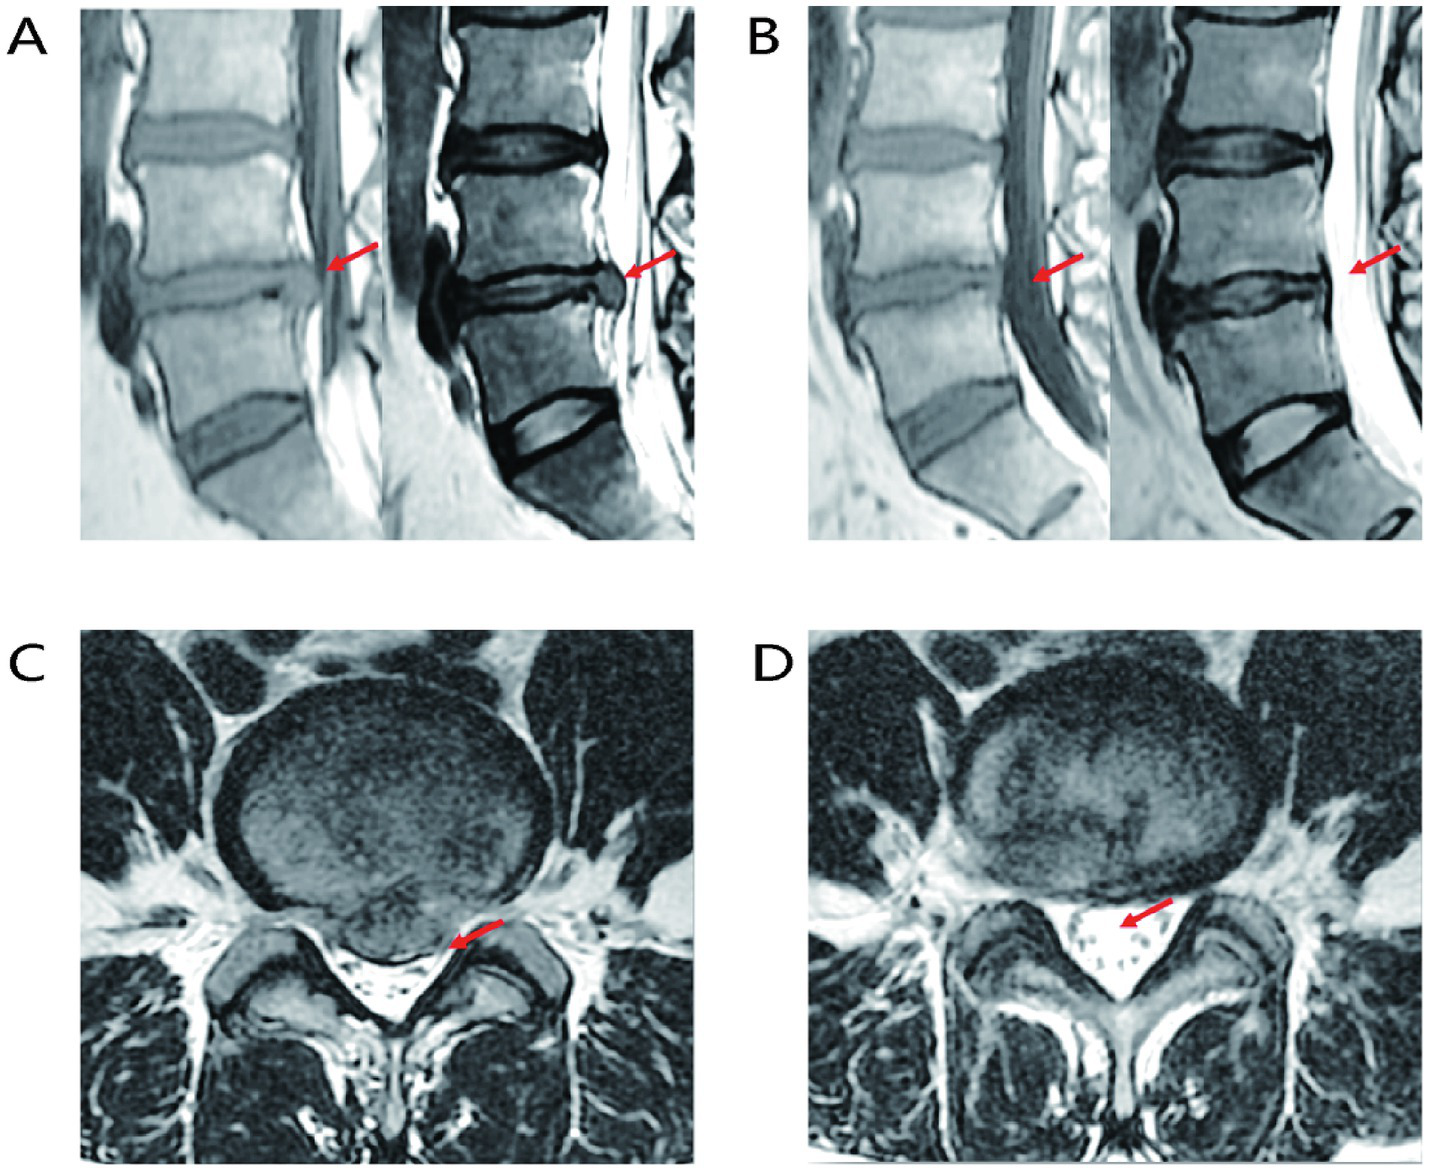

The proposal of the LDH reabsorption theory is closely associated with advancements in imaging technologies. LDH reabsorption was first observed through CT in 1984 and subsequently received more extensive investigation with the advancement of MRI techniques (22–24), gradually becoming an essential standard for diagnosing LDH and related lumbar intervertebral disc (LIVD) (25). MRI images demonstrate that as the peripheral signal ring around the protrusion intensifies, greater edge thickness corresponds to higher signal intensity. Significant enhancement of reabsorption at the margins of protruded tissue is an important factor for evaluating spontaneous regression of IDH (26–28), as shown in Figure 2. LDH tissues have a high cartilage content, and subtle changes associated with reabsorption can be detected by MRI. During the natural progression of LDH, imaging features of protruded tissues play a critical role in determining reabsorption status. When LDH tissue has a relatively high cartilage component or when MRI displays only subtle changes, spontaneous LDH absorption is usually impeded. Conversely, if contrast-enhanced MRI reveals free IVD fragments breaking through into the epidural space, an autoimmune response can be stimulated, inducing inflammation and subsequently leading to peripheral granulation tissue formation with annular enhancement. Notably, the non-enhancing free IVD fragment, known as the “bull’s eye sign,” serves as an important imaging marker predictive of favorable LDH reabsorption. Additionally, the greater the proportion of protruded IVD tissue within the spinal canal, the higher the likelihood of reabsorption (29). In summary, MRI is crucial for the diagnosis and evaluation of LDH reabsorption.

Figure 2

Representative MRI images of LIVD reabsorption. (A) Sagittal MRI image of LIVD before treatment. (B) Sagittal MRI image after LIVD reabsorption. (C) Axial MRI image of LIVD before treatment. (D) Axial MRI image after LIVD reabsorption.